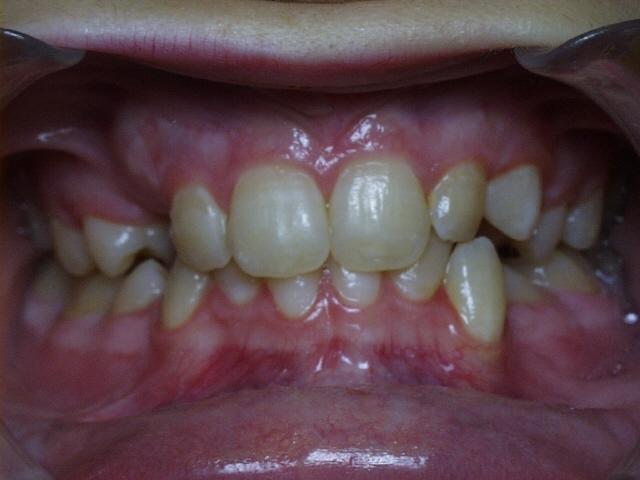

Moderate crowding with a severe overbite.  Treatment time was 20 months.  This case required the extraction of two upper permanent teeth.  The molars were class 2 (upper molars too far forward at the start of treatment).